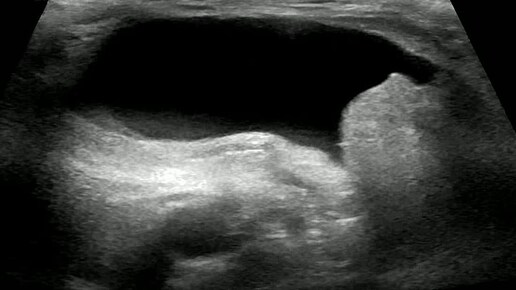

Видео к статье: Гидроцеле канала Нукка. https://dzen.ru/a/aDAxMOvxqQcgJkGG

Ультразвуковые находки от врача УЗД Зорина Я.П.